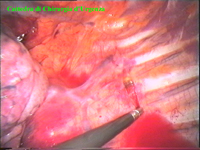

Una volta entrati nel cavo pleurico si attende il collasso spontaneo del polmone. Si identifica il decorso al di sotto della pleura parietale (freccie). La pleura è stata aperta e all’interno della finestra creata si identificano la catena (freccie verdi) e i rami comunicanti (freccie blù). La catena è stata sezionata e con la pinza si esercita una trazione sulla parte caudale.

Sotto controllo visivo si procede alla riespansione del polmone e si controlla il posizionamento del drenaggio. Normalmente la secrezione è talmente scarsa che non è necessario posizionare routinariamente un drenaggio. Terminato l’intervento su di un lato si procede nel cavo pleurico controlaterale. Le freccie indicano il decorso della catena gangliare. La catena è stata sezionata e si esercita una trazione sulla porzione residua in direzione caudale. Controllo della riespansione del polmone.